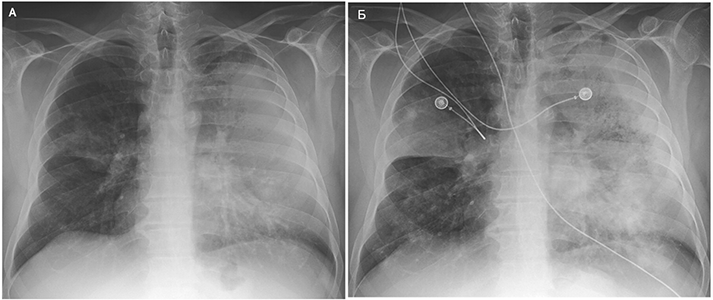

Острая внебольничная пневмония по МКБ-10: признаки и примеры